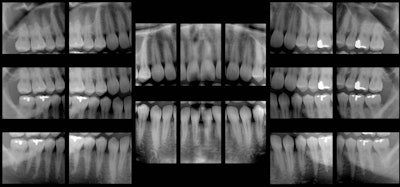

The pros and cons of panoramic bitewingsAug 1, 2012 These panoramic bitewings took 15 to 20 seconds to create, compared with 20 minutes for a full-mouth intraoral survey (Dentomaxillofacial Radiology, January 2010, Vol. 39:1, pp. 47-53). close Latest in HomeIowa dentist, charged with incompetence, surrenders licenseOctober 16, 2025Breastfeeding may not be a risk factor for caries, but these areOctober 16, 2025Dental endoscopy: A hygienist's perspective on transforming periodontal careOctober 16, 20251st known case of high blood pressure drug-induced toothacheOctober 16, 2025